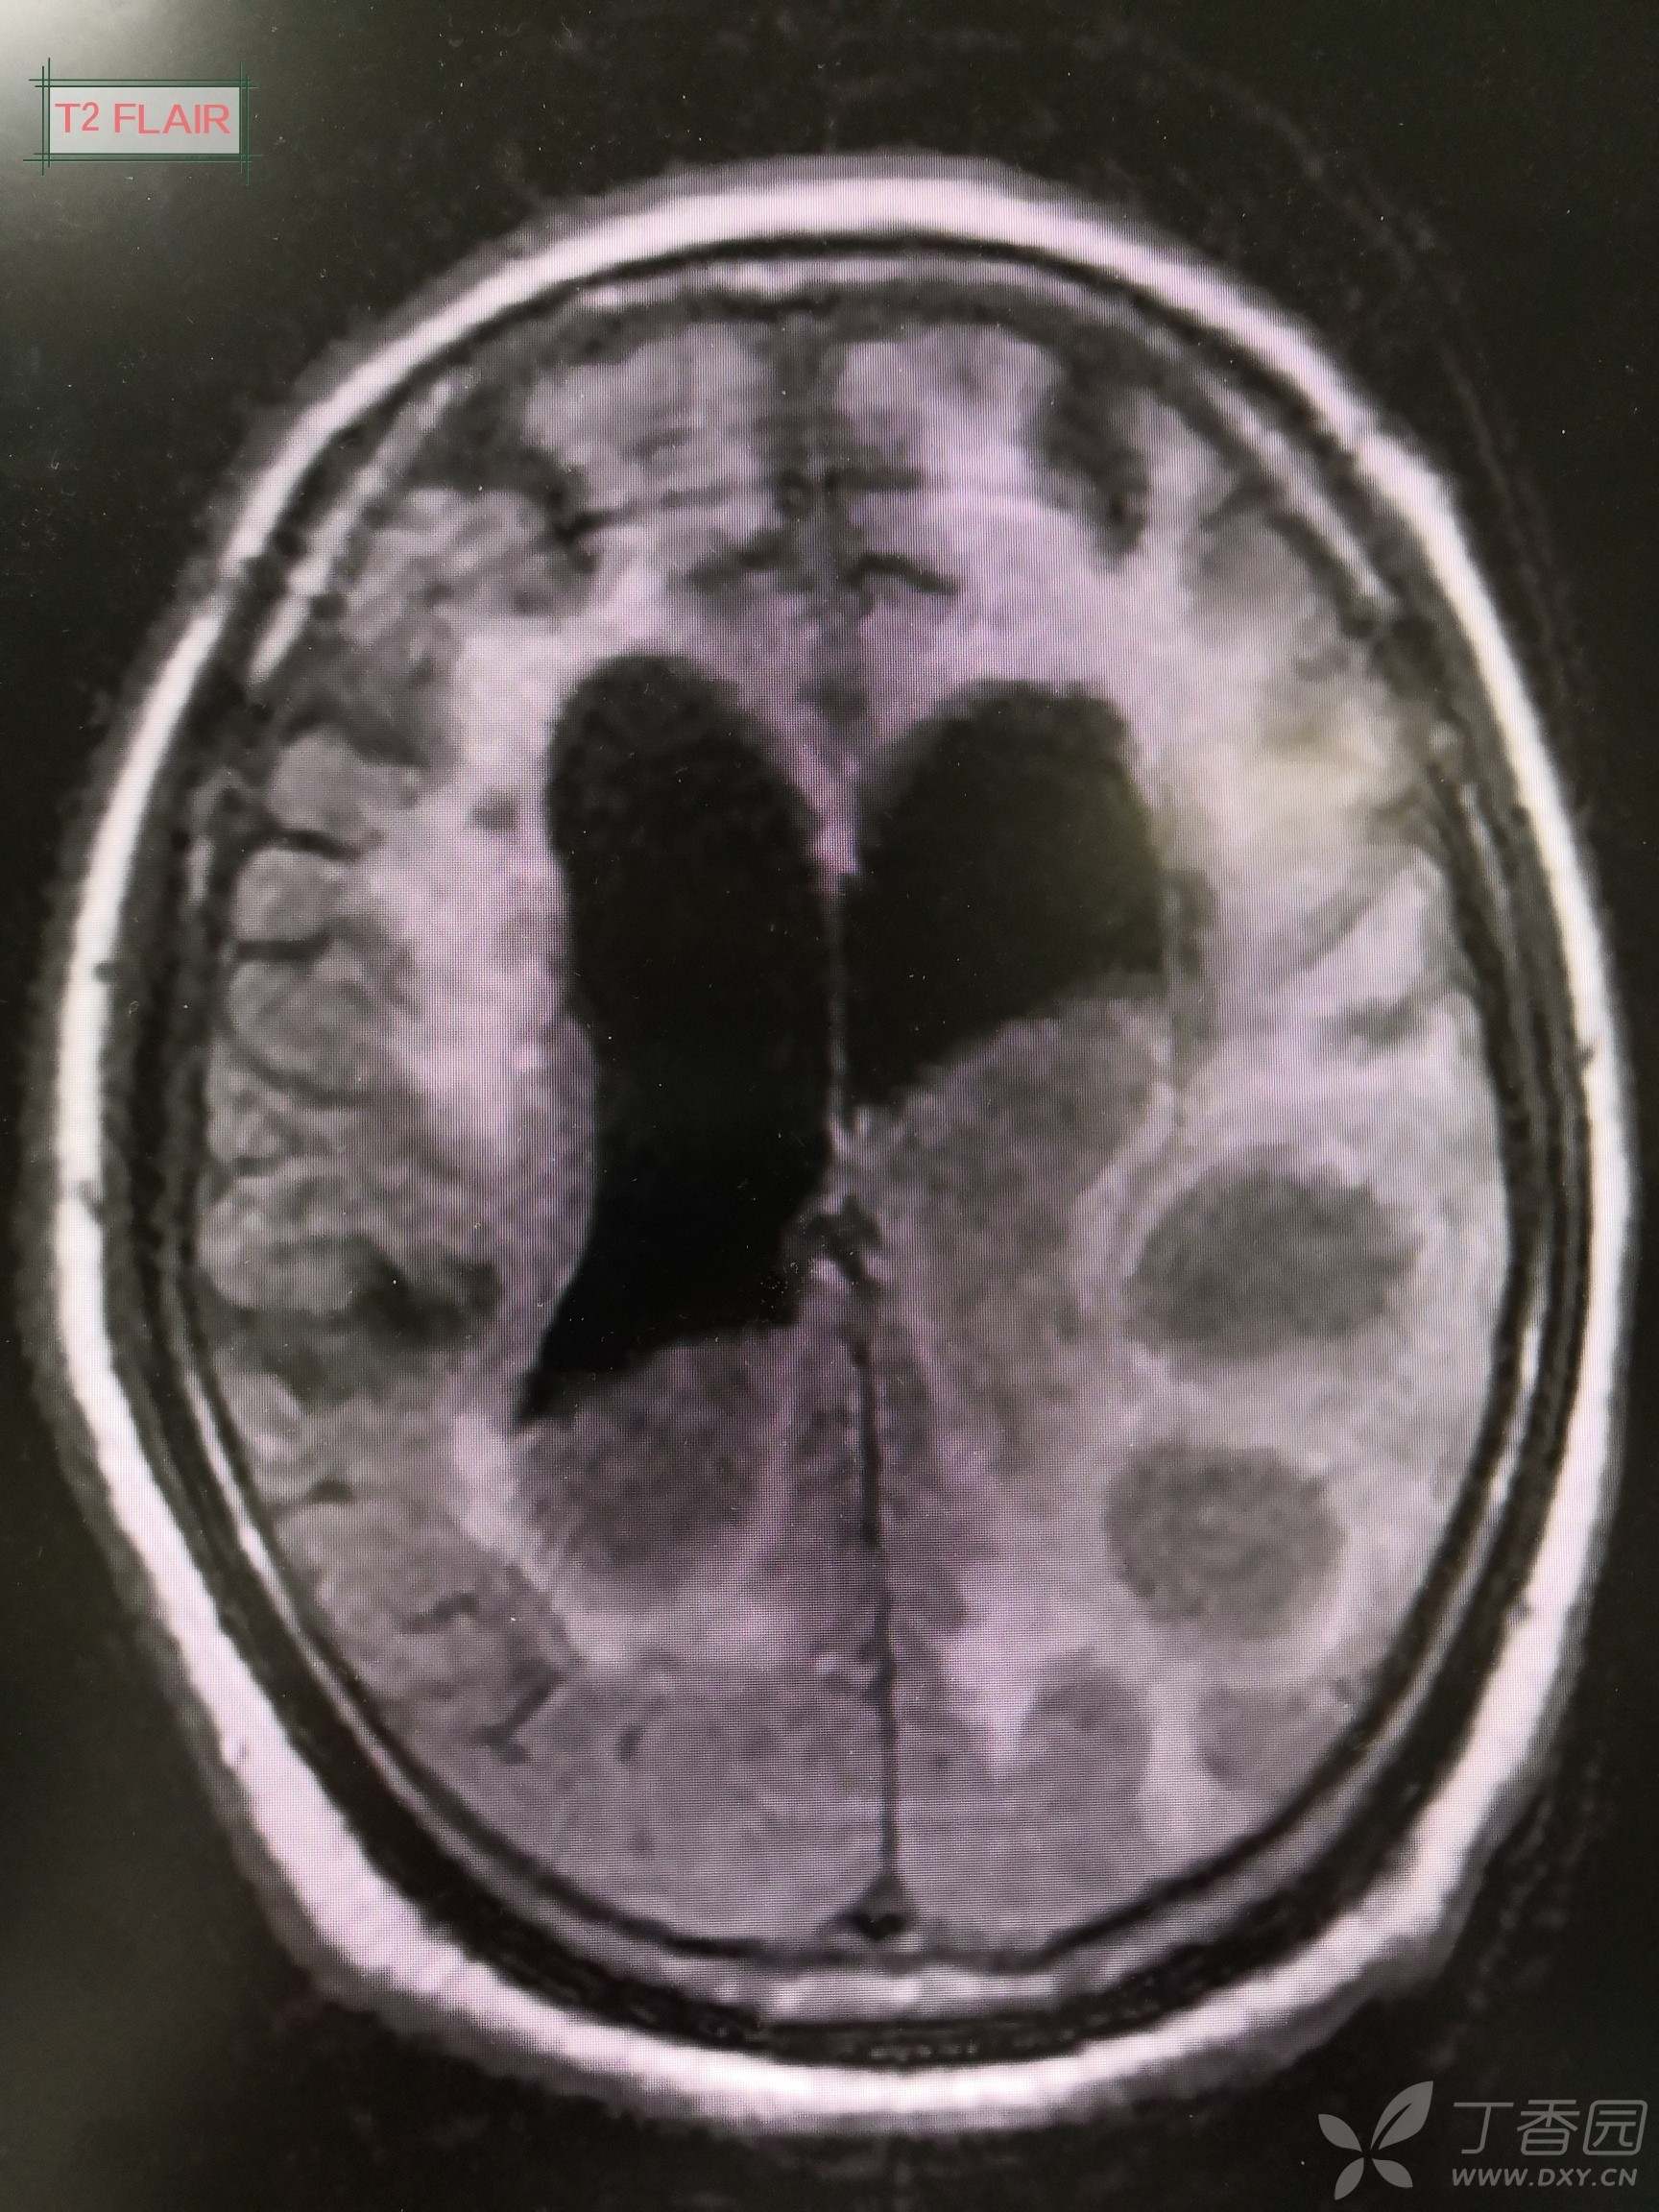

会诊意见:头颅磁共振结果回报后再次请神经外科及影像科会诊:左顶叶多发类圆形病灶DWI呈高信号,长T1长T2信号,FLAIR呈等信号,MRI增强扫描环形强化。左侧顶叶类圆形占位性病变符合脑脓肿影像学表现,考虑脑脓肿,建议抗感染基础上外科干预,侧脑室穿刺引流+冲洗,但基础疾病多,预后差。